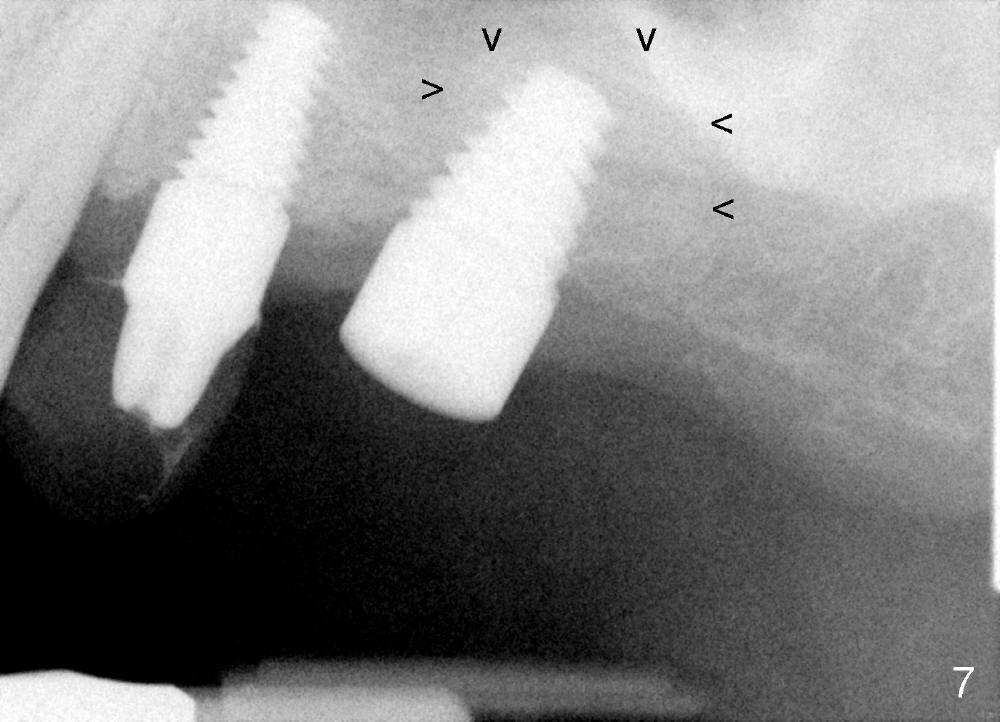

Bone graft remains in place 2 months postop (Fig.7 arrowheads); its density increses 4 months postop (Fig.8). The gingiva around the implant and abutment at the site of #14 is healthy (Fig.9 (4 months postop before final impression);10 (5 months postop immediately before final cementation)).